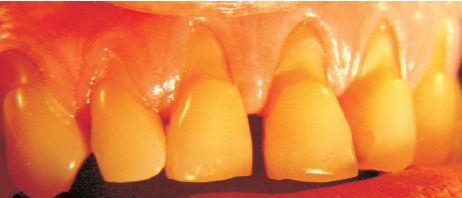

Fig. 7

Fig. 8

Figs. 7 y 8. Paciente de 63 años, sexo masculino. Erosión rampante en todos los dientes inferiores con algunas facetas de contacto. Se observan sobresaliendo islotes de amalgama. Aparentemente actividad ácida exógena, causada por dieta o factores medioambientales hasta el momento no detectados. Resumiendo: erosión ácida idiopática, con atricción sobreagregada